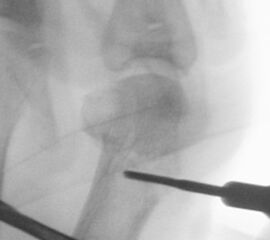

• Positionierung des Bildwandlers: 90° Winkel zum Os metatarsale I. Benötigt wird die Durchleuchtung des Vorfußes a.p., seitlich und schräg.

Zum Lesen der Bildbeschreibung und zur Vollansicht bitte die Bilder anklicken.